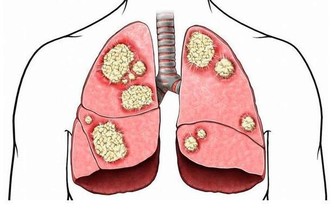

4.患有疾病

頭髮變白,也可能是某些疾病的徵兆,如白血病會導致頭髮變白。